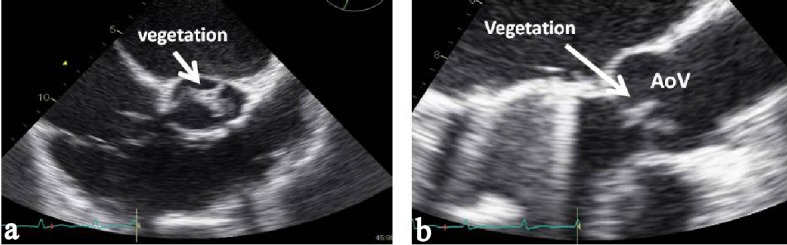

Infective endocarditis due to non-toxigenic | is uncommon. We describe the case of a 42-year-old male with a history of mitral valve replacement with prosthetic valve for 4 years. He presented with fever, weight loss, dyspnea on exertion and orthopnea. The echocardiography demonstrated large vegetation attached on the left coronary cusp of the aortic valve with moderately severe aortic regurgitation but sparing of the prosthetic mitral valve. Three separate blood cultures grew | species. The patient underwent aortic valve replacement due to valvular dysfunction and congestive heart failure. | DNA was detected by 16 S rDNA polymerase chain reaction (PCR) from the heart valve tissue. The patient recovered completely with combine antibiotics and surgical intervention. He was discharged from the hospital with good clinical outcome.